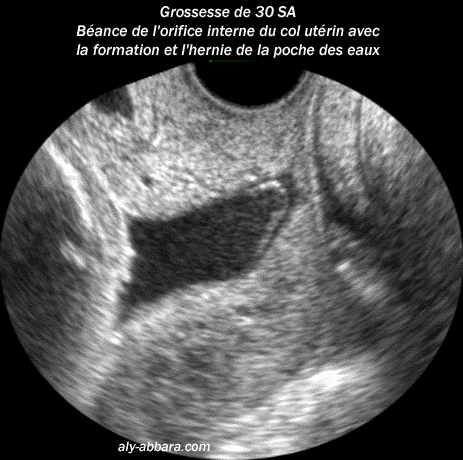

Coupe sagittale passant par le col utérin à 30 semaines d'aménorrhée

Il s'agit d'un col long de 35 mm avec orifice interne et externe béants et une hernie

de la poche des eaux dans le canal endocervical.